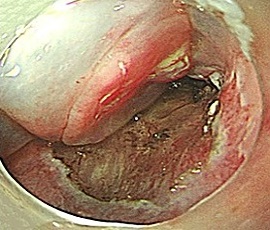

粘膜下層剥離

剥離終了